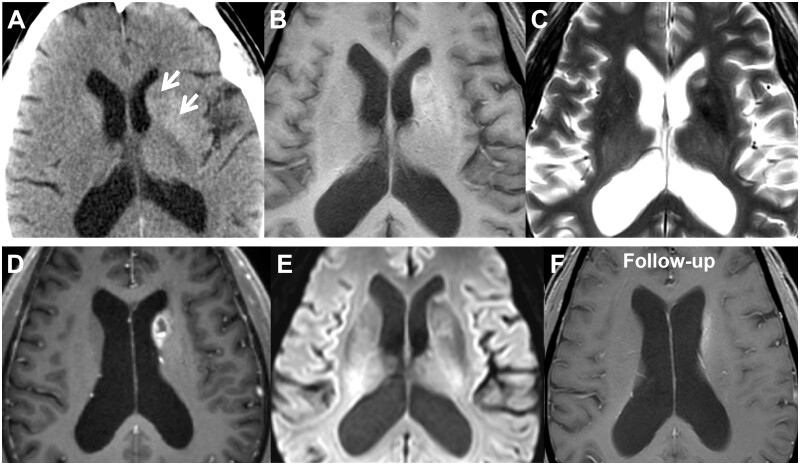

Non-ketotic hyperglycaemia (NKH)-induced hemichorea-hemiballismus (HC-HB) is an infrequent reversible condition observed in individuals with poorly controlled diabetes. In this report, we present a case of NKH-induced HC-HB exhibiting distinctive morphological and functional alterations on conventional magnetic resonance imaging (MRI), diffusion-weighted imaging (DWI), and 1H magnetic resonance spectroscopy (MRS), followed by subsequent monitoring. A 70-year-old male with a 20-year history of diabetes presented with severe unilateral involuntary movement. Computer tomography revealed heightened attenuation in the left putamen and caudate nucleus. The conventional MRI revealed the presence of focal T2-hyperintensity, noticeable mass effect, and ring-like enhancement, which are indicative of glioma. Additionally, the DWI showed unrestricted diffusion of water molecules within the lesion. MRS analysis further demonstrated significantly elevated lactate (Lac) and lipids (Lip), minimal increased choline (Cho), basically stable creatine (Cr), and modest decreased N-acetylaspartate (NAA) levels (which remained larger than both Cho and Cr peaks), leading to a diagnosis of NKH-induced HC-HB. This report emphasizes the significance of acknowledging that NKH-induced HC-HB can manifest with imaging features that bear resemblance to those of glioma. The presence of a slightly elevated Cho/NAA ratio alongside a notable increase in Lac/Lip peak on MRS may aid in ruling out neoplastic conditions.